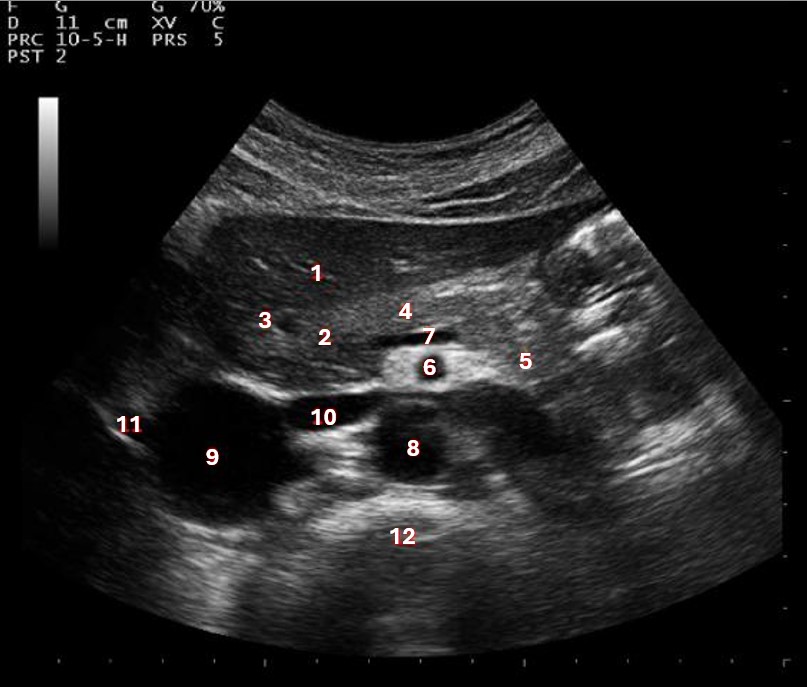

Which of the following structures is labeled #5?

lateral left lobe |

What lobe of the liver is indicated by #1?

posterior right lobe

What structure/vessel is indicated by #8?

medial left lobe |

What lobe of the liver is indicated by #2?

anterior right lobe |

Which of the following structures is labeled #7?

anterior right lobe |

What structure/vessel is indicated by #12?

spine

Which of the following structures is labeled #6?

medial left lobe |

Which of the following structures is labeled #3?

IVC

Which of the following structures is labeled #8?

posterior right lobe |